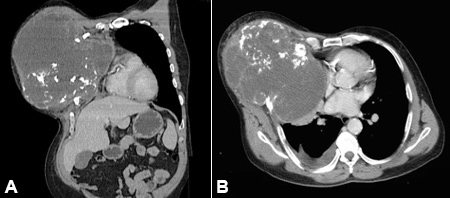

Previous ipsilateral rib fractures without other remarkable medical history were found. A computed tomography (CT) scan was performed, which was consistent with a CWC affecting the third to sixth right ribs, with a mass-effect on the mediastinum structures, the heart (mainly the right atrium), and a partial collapse of the right lung lobes (Figure 2).

The case reported herein presents peculiar and interesting features of CWC management and thoracic reconstruction. Besides being a rare entity, this chondrosarcoma’s dimensions are markedly larger than those reported in the medical literature, considering an average tumor volume of 311–611.5 cm3 (range: 1.5–6,372 cm3) and an average resection area of 81.6–266 cm2.2,9,12,13 Clinical presentation with a painless mass is unusual (about 25% of cases), especially in large tumors.2,3,6,13 The typical chondrosarcoma CT findings were present in our case, consisting of a lobulated mass with calcifications—a flocculent or “popcorn” calcification pattern.3 After the diagnosis was confirmed by core needle biopsy, the subsequent treatment was discussed at a multidisciplinary oncologic team meeting. A wide en bloc resection with appropriate margins, bony chest wall reconstruction preserving respiratory mechanics, and vascularized soft-tissue coverage was considered the best option, according to primary CWC recommendations.3-5 Reconstruction of complex full-thickness defects of the chest wall remains a great challenge due to its important role in respiratory function and the protection of vital organs. For skeletal support reconstruction, synthetic materials are currently most commonly used.7-11 The ideal characteristics of prosthetic materials include: rigidity (avoiding paradoxical chest motion), malleability (intraoperative, shaped according to defect), inertness (allowing in-growth of fibrous tissue and preventing infection), and radiolucency (radiographic follow-up).8,10-12 Diverse synthetic materials are available, providing reliable stability and contributing to full recovery after oncologic resection of the chest wall, with associated shorter hospitalization and ventilator time.7,9,11 Polypropylene mesh (Prolene® or Marlex®), combined with MMA in a sandwich technique when additional rigid support was needed, has been frequently used with excellent physiologic and aesthetic outcomes.1,3,9-11 Bioprosthetic meshes, including acellular dermal matrices, are also available, offering a good alternative in defects with a high risk of infection and/or skin dehiscence where the synthetic mesh is contraindicated.8 The reconstructive choice for skeletal support should consider different aspects of the chest wall defect: (i) small defects (<5 cm) or those located posteriorly under the scapula above the fourth rib, may not require skeletal reconstruction 8,10,11,14; (ii) lateral defects more often require mesh reconstruction8,11; (iii) for resection of <4 ribs a mesh-only reconstruction is applied; and (iv) for ≥4 ribs and/or a sternal resection, mesh with MMA is recommended.9 MMA has been widely used for rigid chest wall reconstruction, often applied between two layers of polypropylene mesh in a sandwich fashion, which is modeled to the thoracic curved shape.8,15,16 It is relatively inexpensive, and its rigidity provides excellent stability and coverage of vital structures.15 However, in some studies, MMA was associated with higher rates of seroma and infection requiring removal; problems with anchorage and prosthesis dislocation; and fracture of the MMA edges with associated chronic pain.8,15,16 More recently, titanium prosthetic devices have been used for bridging multiple ribs and/or sternal defects after oncologic resections.16-18 Titanium devices provide a light-weight but strong rigid support for rib fixation and chest wall reconstruction.17 Their advantages include a high strength-to-weight ratio, precise molding, integration with the bone over time, resistance to infection, and low interference with the CT.17,18 Moreover, these titanium devices closely ‘mimic’ the anatomic contour of the ribs, thus better restoring the chest wall shape and allowing more physiologic rib movement and breathing mechanics, compared to what can be achieved with MMA.15,17 However, some complications involving fracture or displacement of the titanium systems were reported.15,16,18 In complex chest wall defects, the reconstruction with titanium devices usually requires combination with synthetic or biological meshes and/or muscle flap coverage.15,17,18